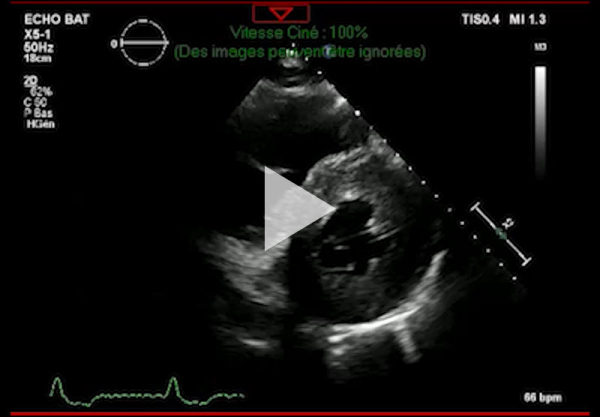

Vidéo 3 - Échocardiographie 2D en incidence parasternale petit axe

Figure 2 : Échocardiographie 2D Coupe parasternale petit axe (mesure des parois VG)

- Ventricule gauche non dilaté, hypertrophie concentrique symétrique majeure non-obstructive, hypokinésie globale, aspect scintillant du myocarde

- FEVG 45- 50 %

- Pressions de remplissage VG probablement élevées

- Dilatation bi-atriale marquée (OG 54 ml/m²)

- Fuite mitrale centrale modérée, épaississement des valves

- Ventricule droit non dilaté modérément hypertrophique

- Fonction systolique VD diminuée

- Hypertension pulmonaire peu probable (Vmax IT 2,85 m/s)

- Décollement péricardique minime inférieur